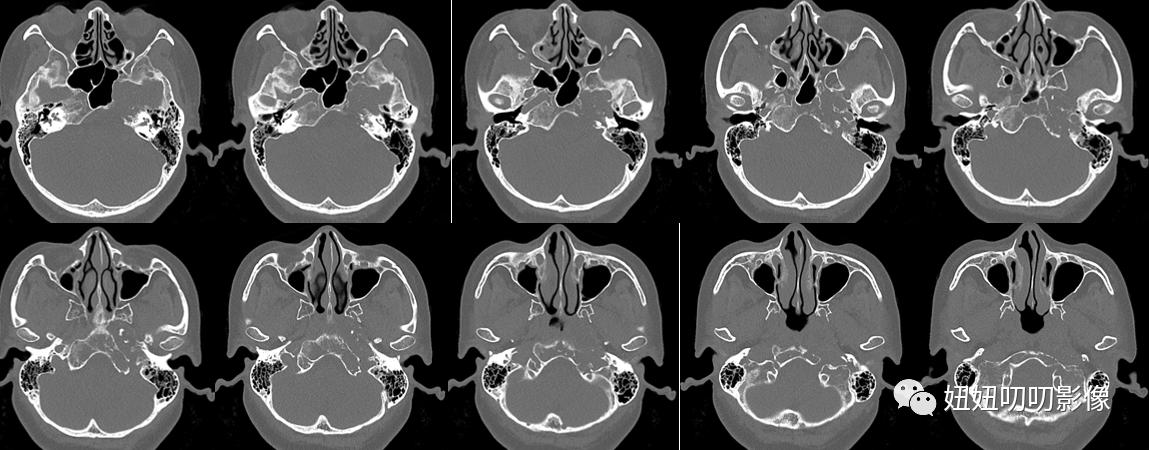

CT:鞍区及左侧岩尖区见不规则形等低密度灶,其内密度不均,可见斑点状致密影,斜坡、海绵窦、颞骨岩部骨质破坏,边界欠清,大小3.6x3.7x4.4m,增强扫描呈轻度不均匀强化,脑桥前缘、垂体、视交叉、左侧颞叶受压移位,左侧颈内动脉、大脑中动脉受压、迂曲增宽。

CT:鞍区占位性病变,软骨肉瘤可能,与脊索瘤等鉴别,请结合病理学检查。